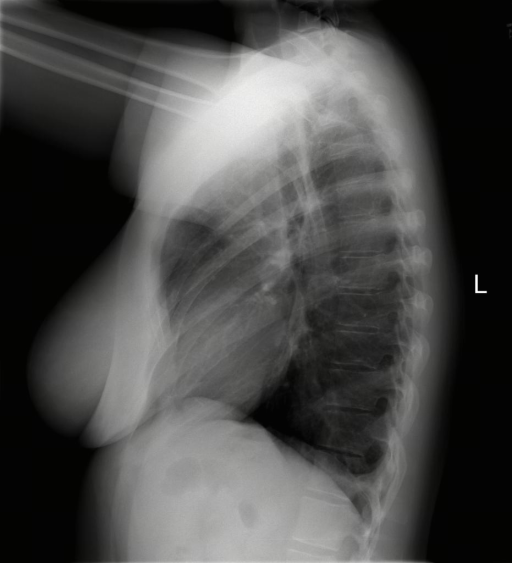

Public Dataset Integration for Breadth. We leverage established open-source datasets (e.g., MIMIC-CXR [28], CheXpert [24], and ROCO [47]) to provide a foundational layer of visual variety. These datasets offer a vast quantity of samples covering common pathologies and standard anatomical views. However, raw annotations in public datasets are often noisy or limited to binary classification tags (e.g., “Pneumonia: Positive”).

Stage 3: Multi-Granularity Instruction Formatting. To enable the model to handle various user intents, we do not simply pair the image with a single caption. Instead, we generate diverse instruction-response pairs derived from the generated caption. These include: (1) Descriptive Instructions (e.g. “Describe the findings in this chest X-ray.”), (2) Diagnostic Q&A (e.g. “Is there evidence of pleural effusion? If so, describe its location.”), (3) Localization Tasks (e.g. “Identify the region responsible for the patient’s shortness of breath.”), and (4) Reasoning Prompts (e.g. “Based on the visual evidence, what is the most likely diagnosis and what follow-up is recommended?”).

The training dataset is built mainly from radiology imaging data (e.g., X-rays, CT scans, MRI) and public de-identified radiology datasets, which include pathological/normal cases, metadata and expert annotations. Given the varying diagnostic complexity and tool utility of raw radiology data, a two-stage filtering pipeline is adopted to create an effective RL training set:

Medical report generation stresses long-form coherence and, more importantly, faithfulness: the ability to describe findings without introducing subtle hallucinations or unsupported claims. Evaluation in this category is particularly sensitive to protocol choices (e.g., what constitutes an omission versus an incorrect addition), which motivates our unified prompting, structured output requirements where applicable, and complementary inhouse faithfulness tests. Tab. 7 lists the report benchmarks included.